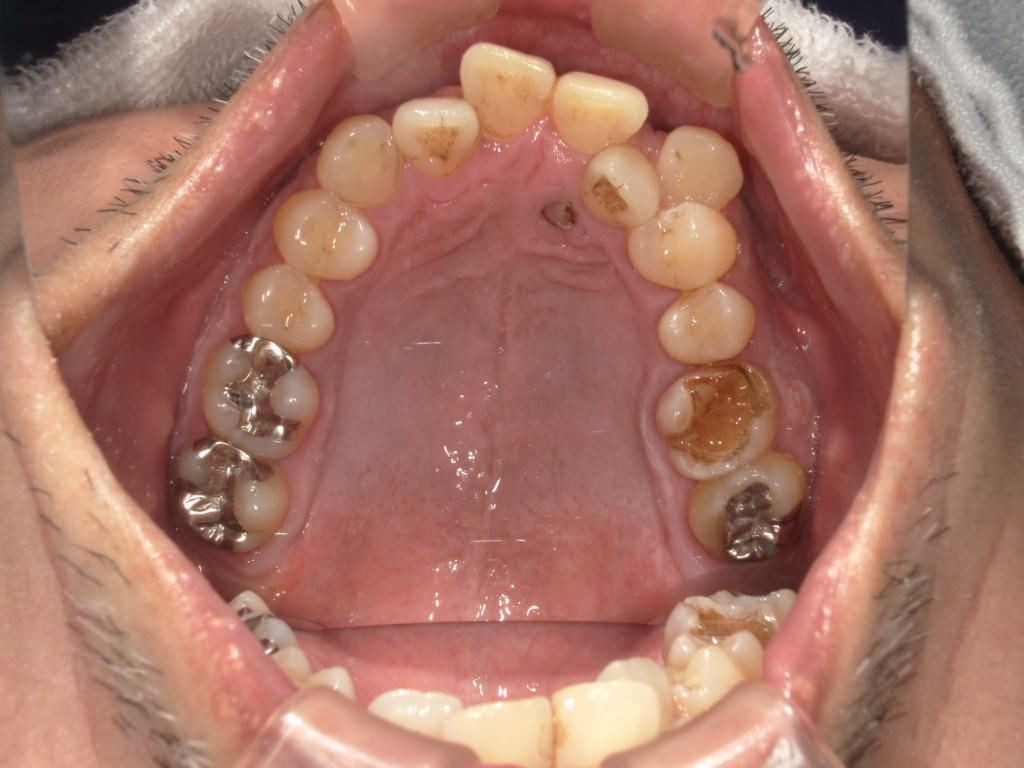

Y様インプラント実例 #44

左の上下の奥歯をインプラントで治療しています。

左下の奥歯は歯を抜くのと同時にインプラントの埋め込みを行っています。

被せものは上下、セラミックスで作っています。

治療前

治療後